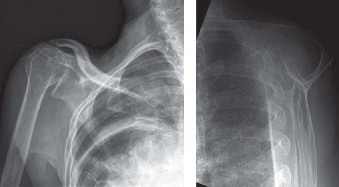

This classification was originally based on CT imaging but is now applied to MRI imaging and uses sagittal oblique views at the most lateral slice in which the scapular spine is continuous with the scapular body. There are five categories that range from stage 0 to stage 4. A classification of stage 0 is normal, stage 1 is some fatty streaks, stage 2 is more muscle than fat, stage 3 is equal amounts of fat and muscle, and stage 4 is more fat than muscle. This patient’s rotator cuff tear involves the supraspinatus and infraspinatus, and both have atrophied to the point of having equal amounts of fat and muscle, giving her tear a Goutallier classification of stage 3 (see Table 2–2 and Fig. 2–18). As a general rule, if there is stage 3 or 4 fatty atrophy, rotator cuff repair will not be successful and a reverse total shoulder or tendon transfer would be a better operation.

Figure 2–18_Three different patients showing different stages of fatty degeneration with Goutallier stages. Higher stages are predictive of worse outcomes after rotator cuff repair. SS, supraspinatus; IS, infraspinatus; TM, teres minor; Sub, subscapularis. (From Kuzel BR, Grindel S, Papandrea R, Ziegler D. Fatty infiltration and rotator cuff atrophy. _J Am Acad Orthop Surg. 2013;21(10):613–623.)